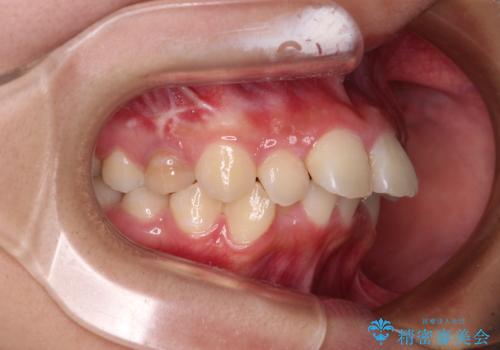

上下前歯が接触しない オープンバイトをインビザラインで改善

- 前歯の上下スペースによる食べにくさを気にして来院された患者様です。

インビザラインにより上下の前歯の隙間を閉じていくこととしました。

上下の奥歯を圧下させるようにすることで、前歯を接触させるように計画しました。

上下の隙間に舌が入り込むことがオープンバイトの原因であったため、舌の筋肉のトレーニングも並行して行い、後戻りの抑制を図りました。